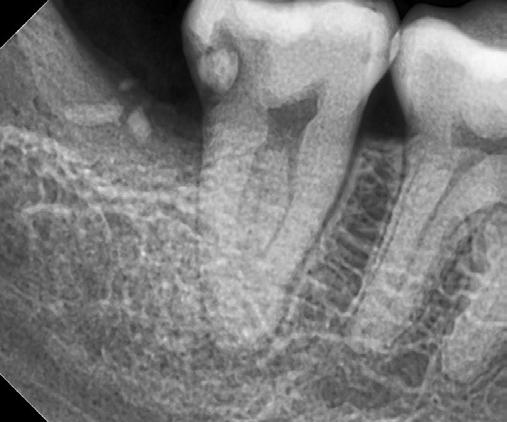

10. ábra: A periapikális felvételen egyértelműen megmutatkozik a 46-os és 47-es fogak között kialakult csontos defektus, valamint a gyökereket fedő parodontális rostok károsodása. – 11. ábra: A disztális gyökér amputációját követően a csonthiány kiterjedése látszólag tovább növekedett. – 12. ábra: A 22 évvel később készített kontrollfelvételen jól megfigyelhető a csontos defektus telődése, valamint új kortikális csontállomány kialakulása.

Gyökéramputációt főként a furkáció érintett nagyőrlő fogak ellátása során szoktunk alkalmazni. Derks és mtsai. vizsgálatában a gyökéramputált nagyőrlő fogak közel 80%-a 20 évvel a beavatkozás elvégzését követően is megtartott volt. 1998 októberében egy 39 éves férfi páciens a jobb alsó kvadránsban jelentkező ínyérzékenység miatt kereste fel rendelőnket. A klinikai vizsgálat során jobb alsó első és második nagyőrlő fog között (46–47) nagy kiterjedésű csontveszteséget észleltünk. Ettől eltekintve a teljes fogazat parodontális státusza megfelelőnek bizonyult. A jobb alsó kvadránsban végzett szenzibilitás vizsgálat során arra az eredménye jutottunk, hogy a 46-os fog vélelmezhetően elhalt (10. ábra).

A páciens beleegyezését követően a 46-os fog disztális gyökere, a disztális gyökér felett lévő koronális rész megőrzése mellett rezekcióra került (11. ábra). A rezekciót követően a referáló orvos a 46. és 47. fogak koronáját Ribbond szalag és kompozit segítségével egymáshoz rögzítette. A sebészi beavatkozást követően 22 évvel készült kontrollfelvételen a lézió csontos telődése, kortikális csontállomány kialakulása, valamint a furkáció körüli csontos regeneráció volt megfigyelhető (12. ábra) A károsodott fogak megtartására szolgáló lehetőségek fejlődésének, valamint az implantátumok behelyezésével kapcsolatos rizikófaktorok jobb megértésének köszönhetően ma már más szemmel vizsgáljuk a fogak eltávolításának szükségességét. A kérdéses prognózissal vagy a kis protetikai értékkel rendelkező fogak eltávolítása előtt mindig érdemes felmérni az ezzel elérhető lehetséges előnyök nagyságát. A kemény- és lágyszöveti pótlás lehetőségeinek fejlődésével, a PRF elérhetőségével, a minimálinvazív sebészeti módszerek és az operációs mikroszkópok elterjedésével, valamint a varróanyagok és varrat technikák egyre kifinomultabbá válásával ma már alaposan el kell gondolkodnunk az előtt, hogy egy fogat egy implantátum behelyezése érdekében eltávolítsunk. Mára sokkal kedvezőbb prognózist és sokkal nagyobb sikerességet tudunk elérni a korábban menthetetlennek gondolt fogak kezelése során.